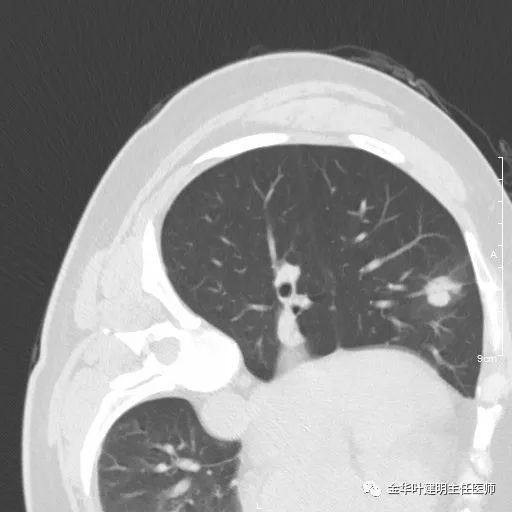

三、浸润性腺癌腺泡型:

影像特征:浸润性腺癌腺泡型的表现,已经是较为典型的恶性,整体上基本是实性密度,但腺泡型的腺癌,其收缩力弱,胸膜凹陷或毛刺征少见,最主要的特点是 密度不均的实性结节 ,边缘可略模糊,但整体病灶的轮廓比较清楚,感觉在正常肺组织区域比较突兀的出现一个实性病灶,缺乏平常认为的空洞、毛刺、分叶、牵拉等典型肺癌的影像征。此型有时与慢性炎或肉芽肿可能会不易区分,适当抗炎治疗后复查对比可能是可以选择的方案之一。